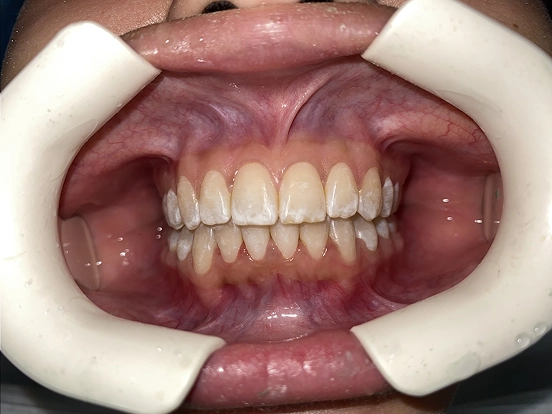

Invisalign DT

DT’s transformation with Invisalign is a perfect example of how advanced orthodontic technology can deliver incredible results. The clear aligners gradually corrected the alignment and bite issues, creating a straighter, healthier, and more attractive smile—all without noticeable brackets or wires.